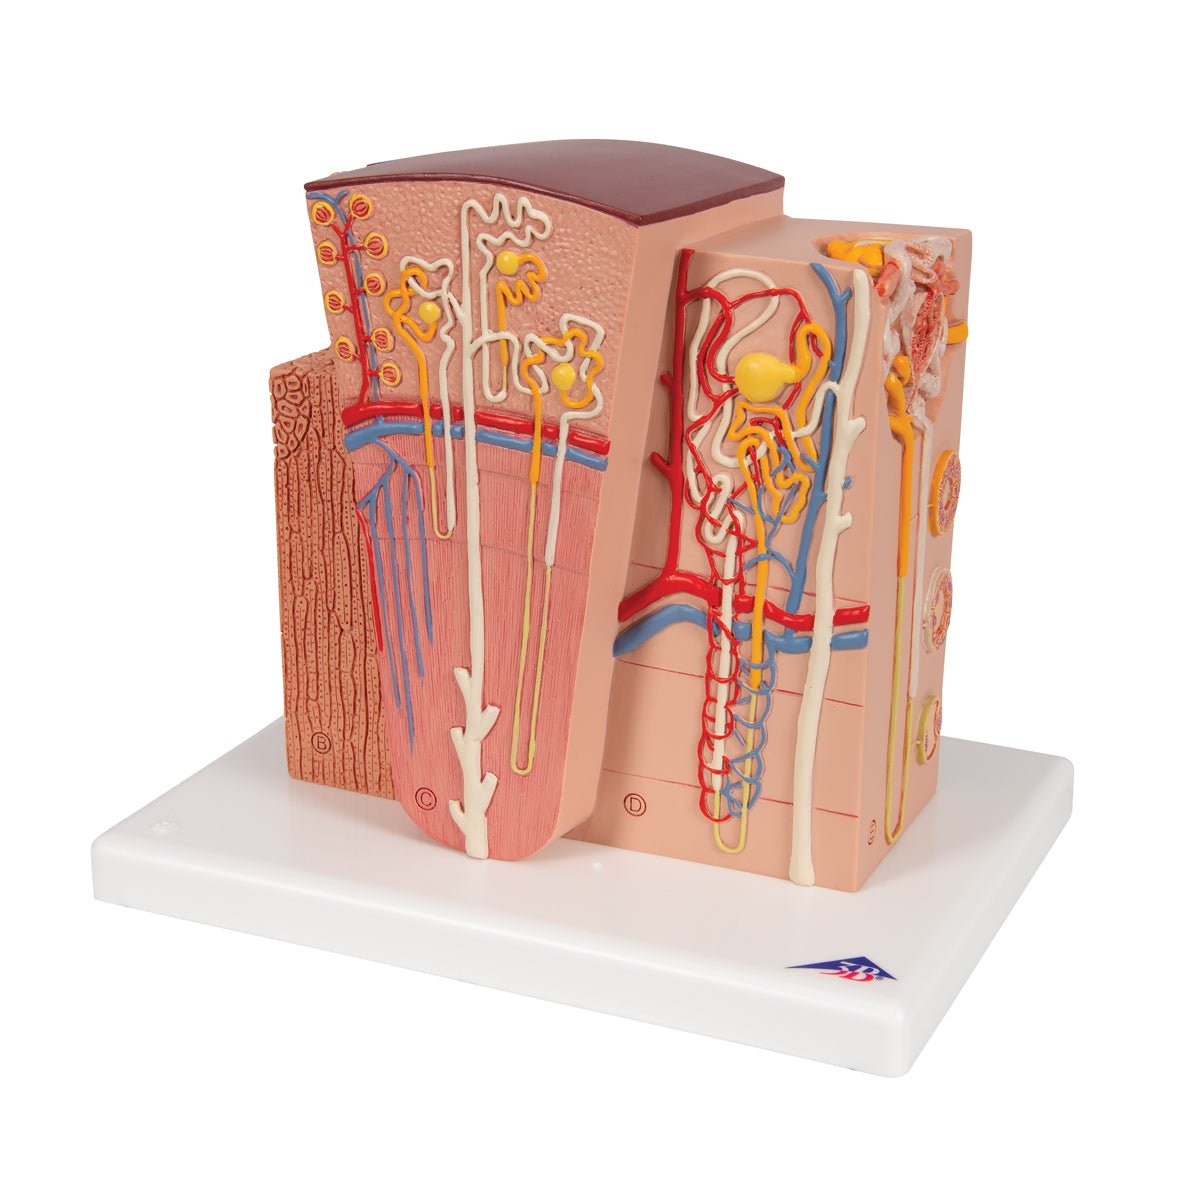

Salg af anatomiske modeller er det bærende element i eAnatomi, selvom vi også bruger mange ressourcer på at udvikle vores egne anatomiske materialer som fx plakater. Anatomiske modeller anvendes til forskellige formål og kan både vise afgrænset væv, organer samt organsystemer. Søger du en simpel model af knoglevæv eller måske en avanceret torso-model baseret på MRI teknologi, kan du finde det hele på eanatomi.com.